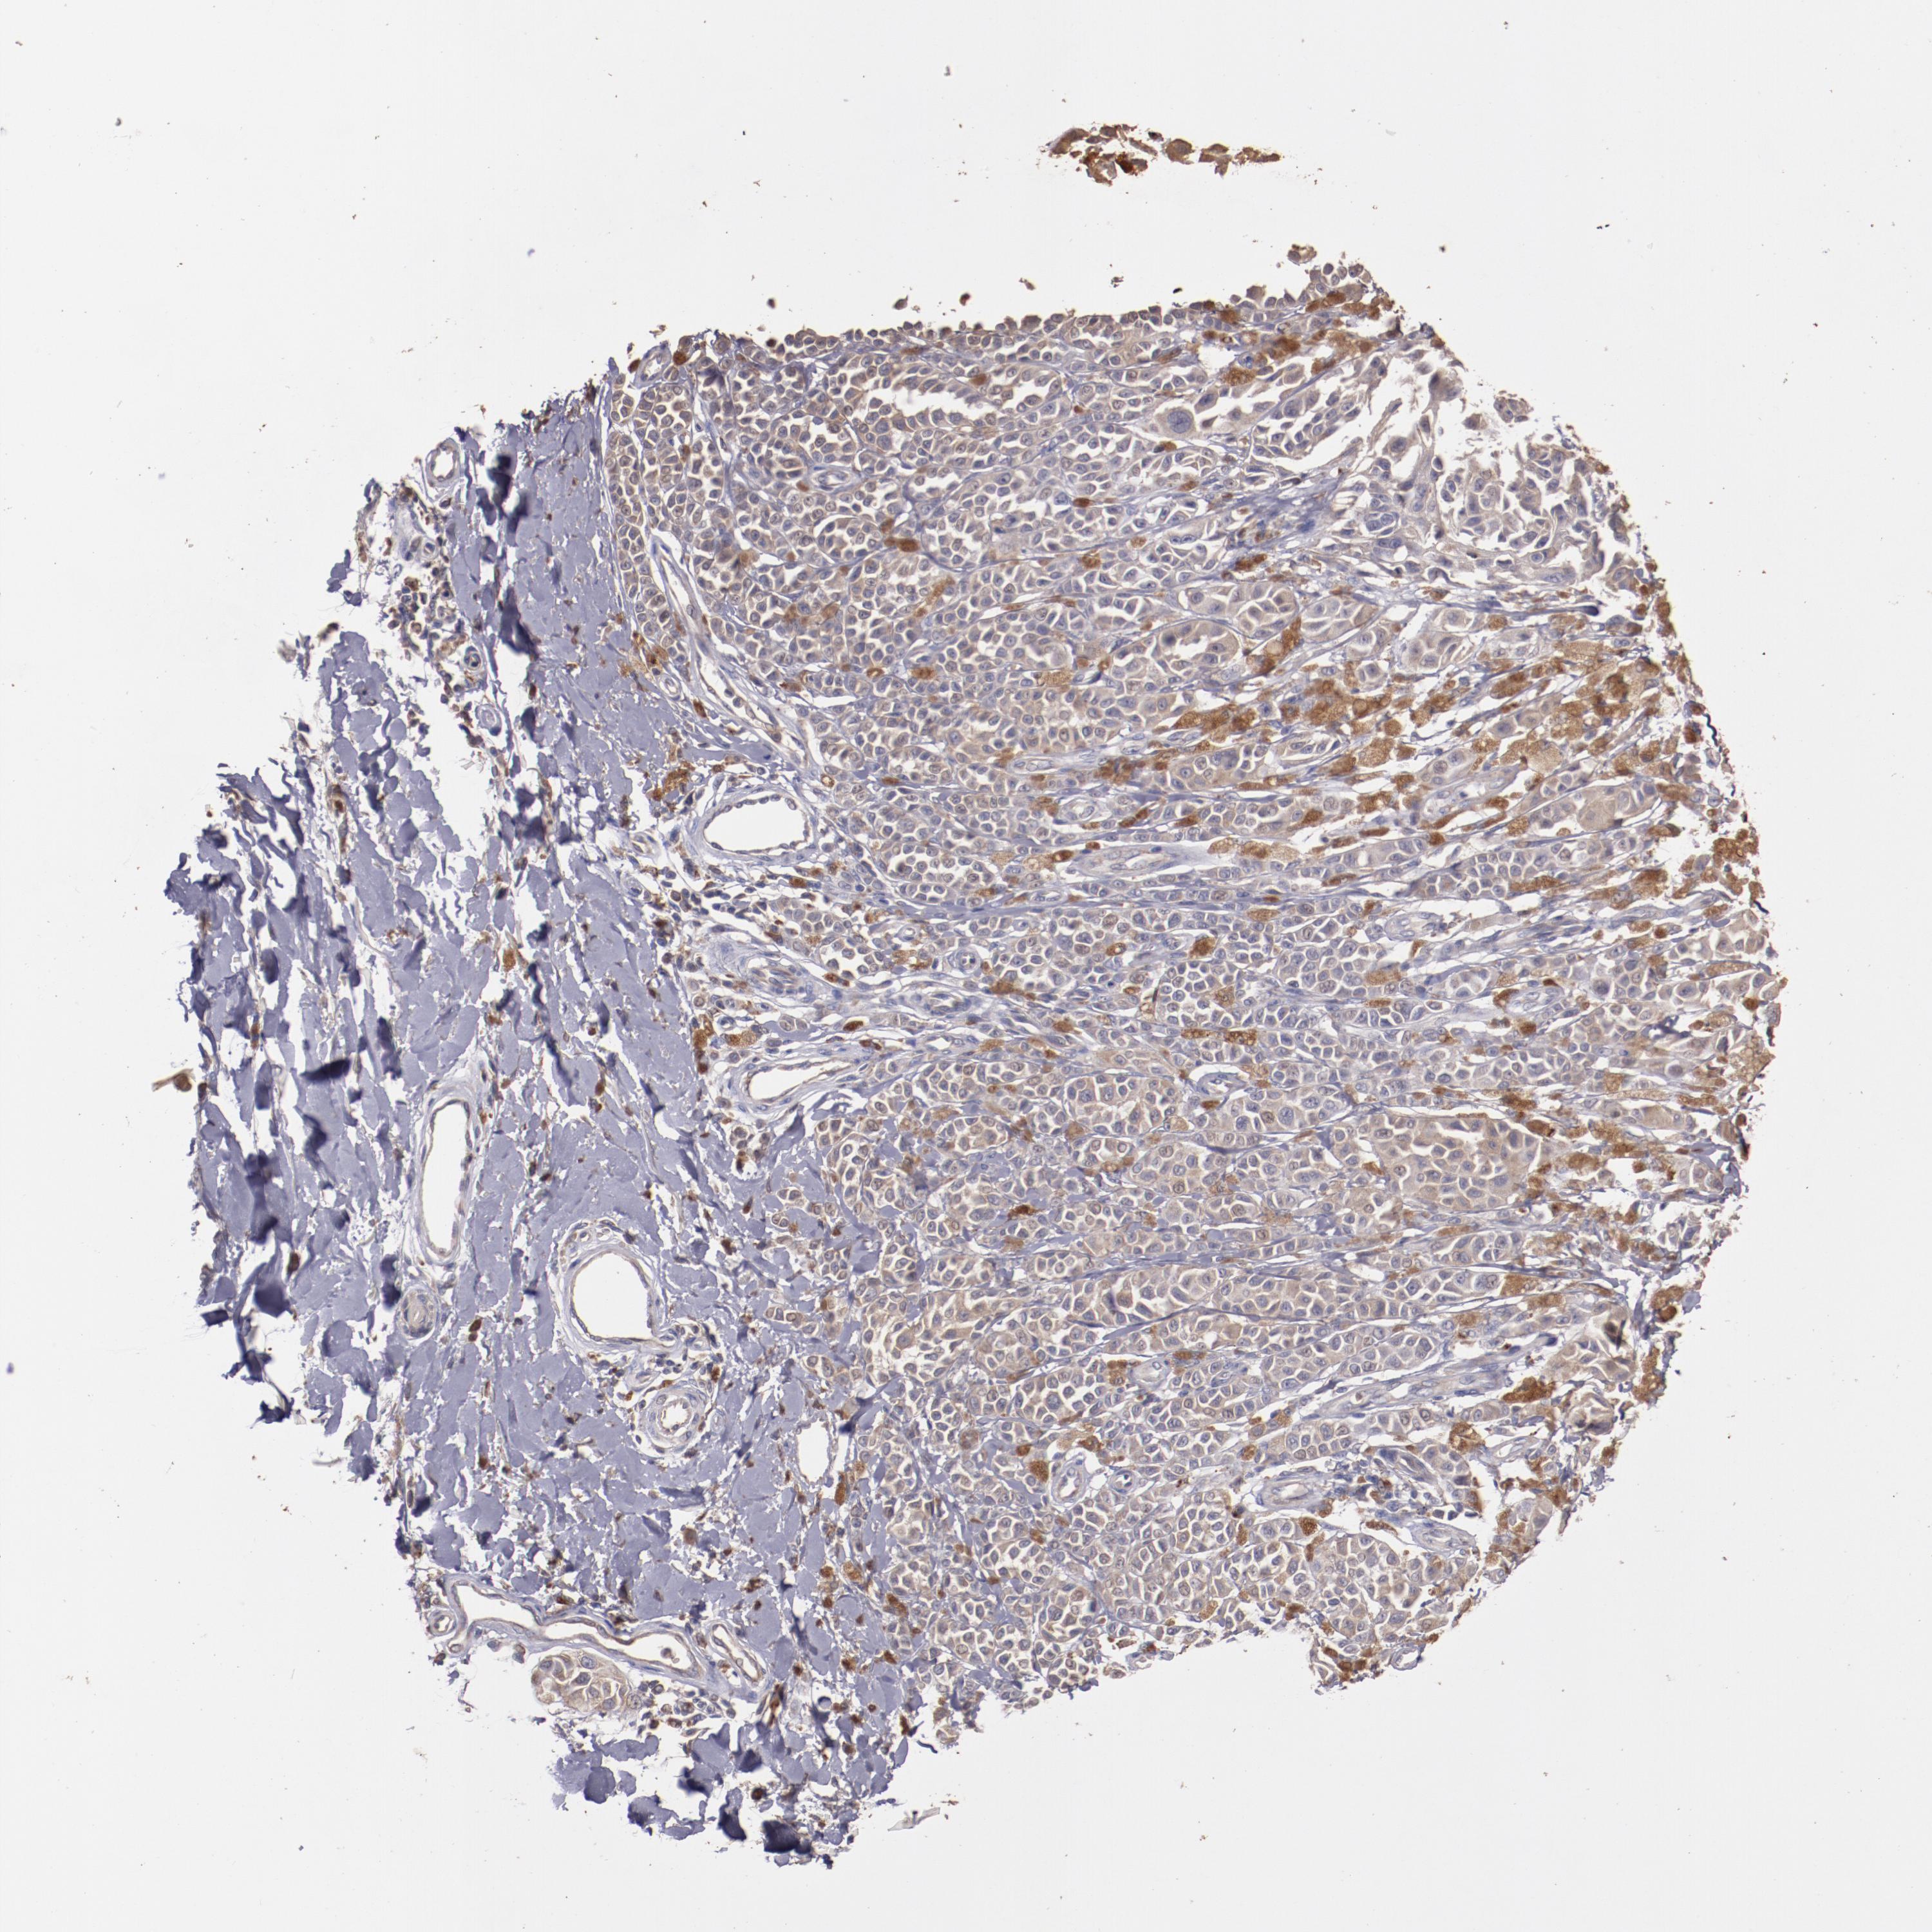

MELANOMA - Protein expressioni

A mouse-over function shows sample information and annotation data. Click on an image to view it in a full screen mode. Samples can be filtered based on level of antibody staining by selecting one or several of the following categories: high, medium, low and not detected. The assay and annotation is described here.

Note that samples used for immunohistochemistry by the Human Protein Atlas do not correspond to samples in the TCGA dataset.

Antibody stainingi

Antibody staining in the annotated cell types in the current human tissue is reported as not detected, low, medium, or high, based on conventional immunohistochemistry profiling in selected tissues. This score is based on the combination of the staining intensity and fraction of stained cells.

Each image is clickable and will lead to virtual microscopy that enables deeper exploration of all samples and also displays staining intensity scores, fraction scores and subcellular localization as well as patient and tissue information for each sample.

Antibody HPA002945

Staining

High

Medium

Low

Not detected

Intensity

Strong

Moderate

Weak

Negative

Quantity

>75%

75%-25%

<25%

None

Location

Nuclear

Cytoplasmic/membranous

Cytoplasmic/membranous,nuclear

Malignant melanoma, NOS

Malignant melanoma, Metastatic site